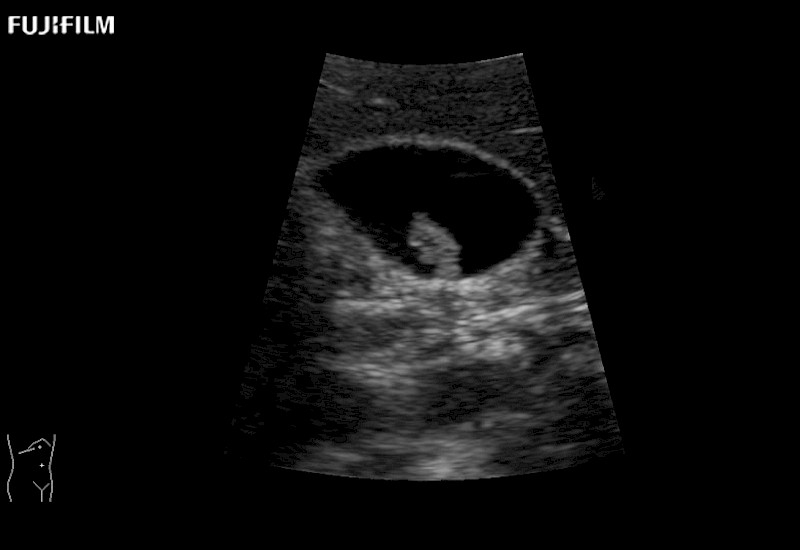

Our dedication to Surgical Oncology allows us to offer superior image quality, outstanding system reliability and intuitive use of cutting edge technology.